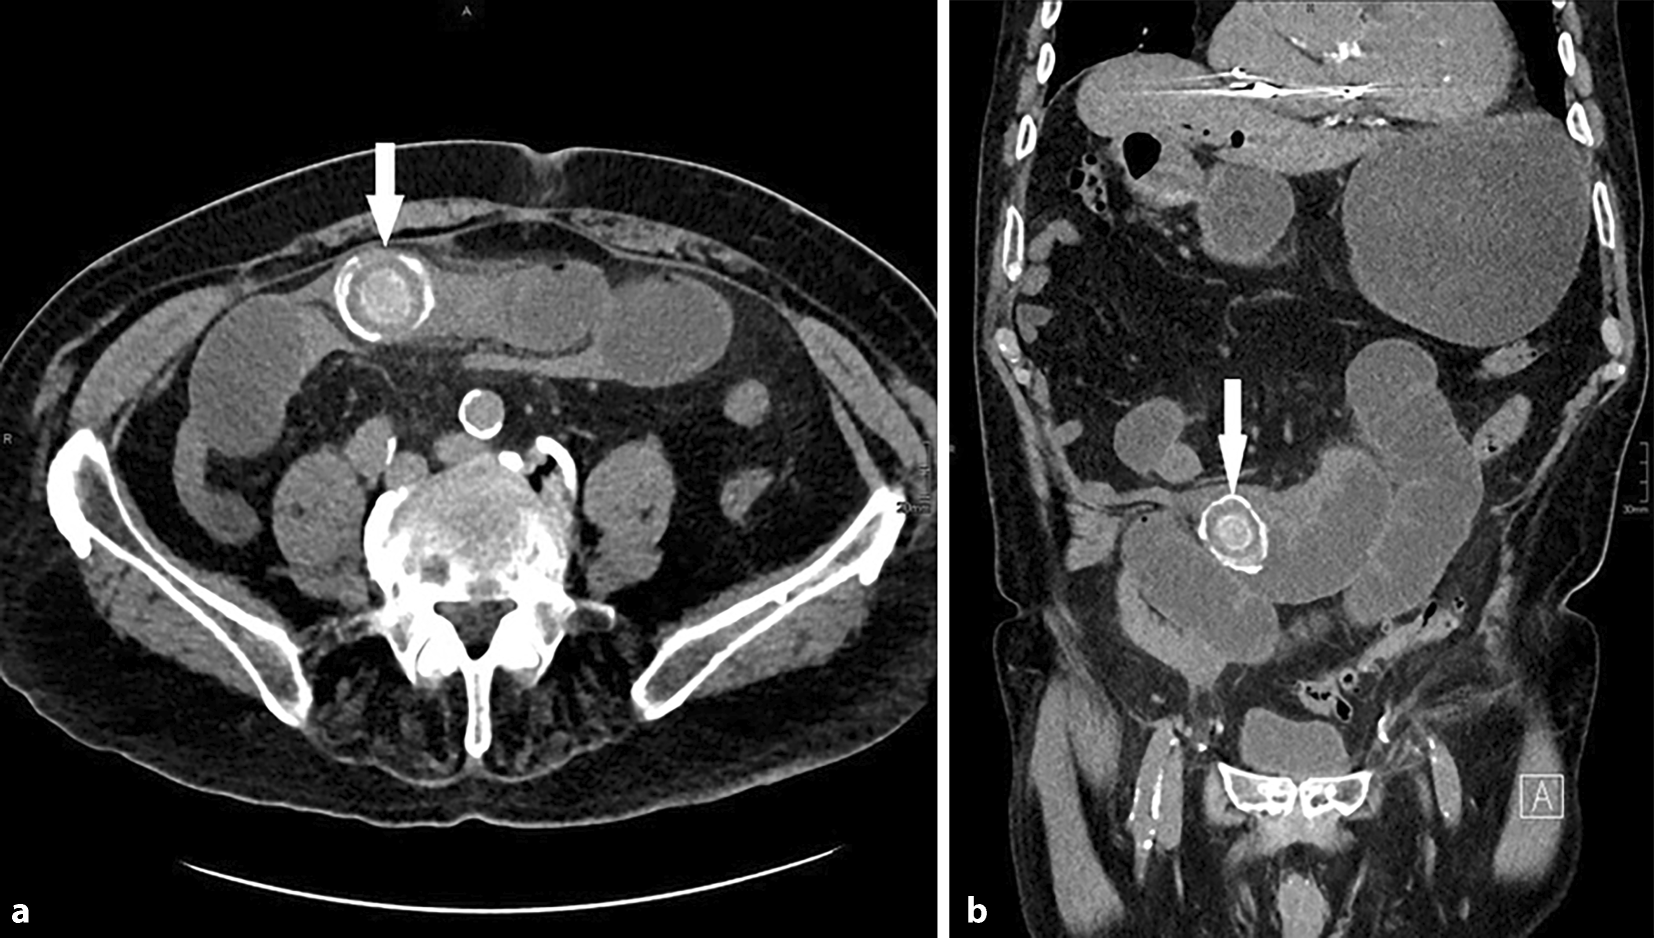

Ein 18 Monate altes Kind hat plötzlich krampfartige Bauchschmerzen und erbricht mehrmals In der Ambulanz zeigt sich ein eher weiches Abdomen und eine tastbare Resistenz im rechten Unter bis Mittelbauch, im Labor finden sich keine Entzündungszeichen Das Kind wirkt lethargisch Die Mutter berichtet über blutigschleimigen Stuhlabgang. Oft gibt es in der Schule für das Kind gar keine offensichtlichen Problemedas zeitliche Auftreten der Bauchschmerzen steht aber klassischerweise für eine emotionale Anspannung im sozialen Umfeld des Kindes Nicht selten folgt der Besuch beim Arzt oder die schulische Entschuldigung, die dann von sofortiger Beschwerdebesserung begleitet wird. PurpuraSchönleinHenoch Weitere Beiträge der Autoren K Gerlach (5) 1 Nebenhodenzyste bei Retentio testis rechts, Hydatide und Hydrocele links 2 Hibernom 3 Darmperforation und Ileus durch Ingestion von Magneten 4 CES kongenitale Ösophagusstenose 5 PurpuraSchönleinHenoch P Göbel (6) 1 Blasendivertikel bei Doppelniere und Ureter duplex.

Funktionelle Bauchschmerzen sind oft daran zu erkennen, dass sich das Kind gut von den Schmerzen ablenken lässt Schluckbeschwerden, anhaltender Durchfall, unklares Fieber oder Gelenkbeschwerden sind wiederum Gründe für einen Arztbesuch, sagt Gunter Flemming, Oberarzt in der KinderGastroenterologie der Universitätskinderklinik Leipzig. Es handelt sich um ein 9 Monate altes Mädchen Ca 2 Stunden vor der Aufnahme waren plötzlich krampfartige Bauchschmerzen mit anhaltendem heftigem Schreien aufgetreten Das Kind fand sich in deutlich reduziertem Allgemeinzustand, war zuvor gesund, gut ernährt und altersgerecht entwickelt. Bauchschmerzen, Schmerzen im Mittelbauch bei Kindern Liste der Ursachen von Bauchschmerzen, Schmerzen im Mittelbauch bei Kindern, Diagnose, Fehldiagnose, Symptome, und Symptomprüfer.